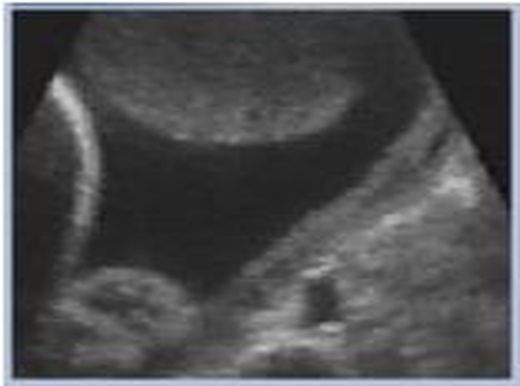

• Investigation of blood flow in vessels by Doppler Effect of UltraSound

Using an ultrasound system for imaging allows as to investigate blood flow velocity parameters. By measuring the blood flow close to the partition, we are able to detect narrowing in the vessel.

Ultrasound imaging systems provide, a medical doctor with a real time imaging system, which also has spectral analysis, and flow speed metering capabilities.